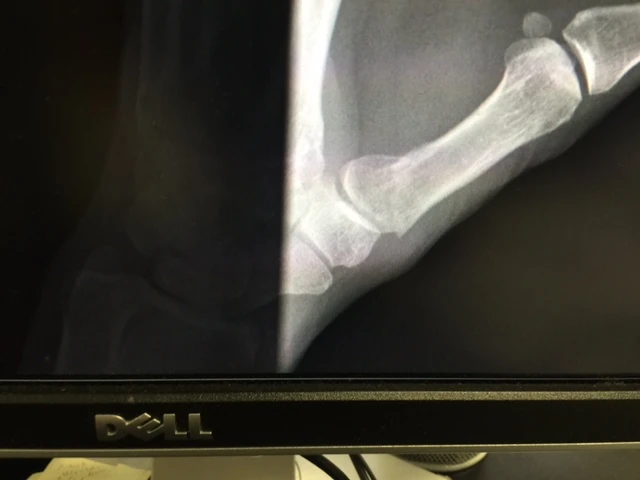

I went to see Stacie yesterday in Louisville. She took a few x-rays and it was sort of a good/bad report. My main concerns, my left thumb and neck seemed pretty good. But my left ring fingers is displaced. Plus, the thumb on my right hand, that I broke before Berryman Epic, is still sort of healing.

My left thumb is what is keeping me from really doing normal stuff. Well, maybe not completely. It is funny how I haven’t really been paying much attention to my left ring finger and now that I see that it is broken badly and probably should have been pinned back together, it is bothering me a ton more.

Stacie talked to a hand surgeon and send him my x-ray and he said that there really isn’t enough bone on the finger to pin it back together. The break is too close to the joint. He said I should be ready for arthritis down the road. That joint and all my others it seems.